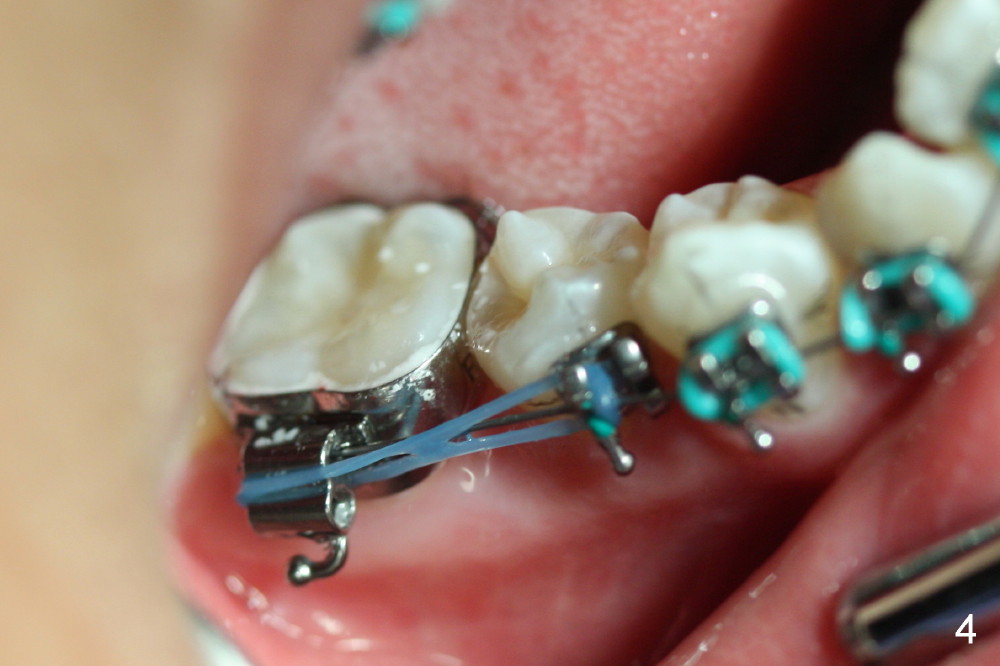

Joshua, 11 years old, has dental crowding (Fig.1), particularly in the lower arch (Fig.3) with molar Class I relationship (Fig.2). The lower 5s rotate (Fig.2 black lines), which are corrected with power chains (Fig.4,5) after bracketing and placing .012" niti wires (Fig.6).